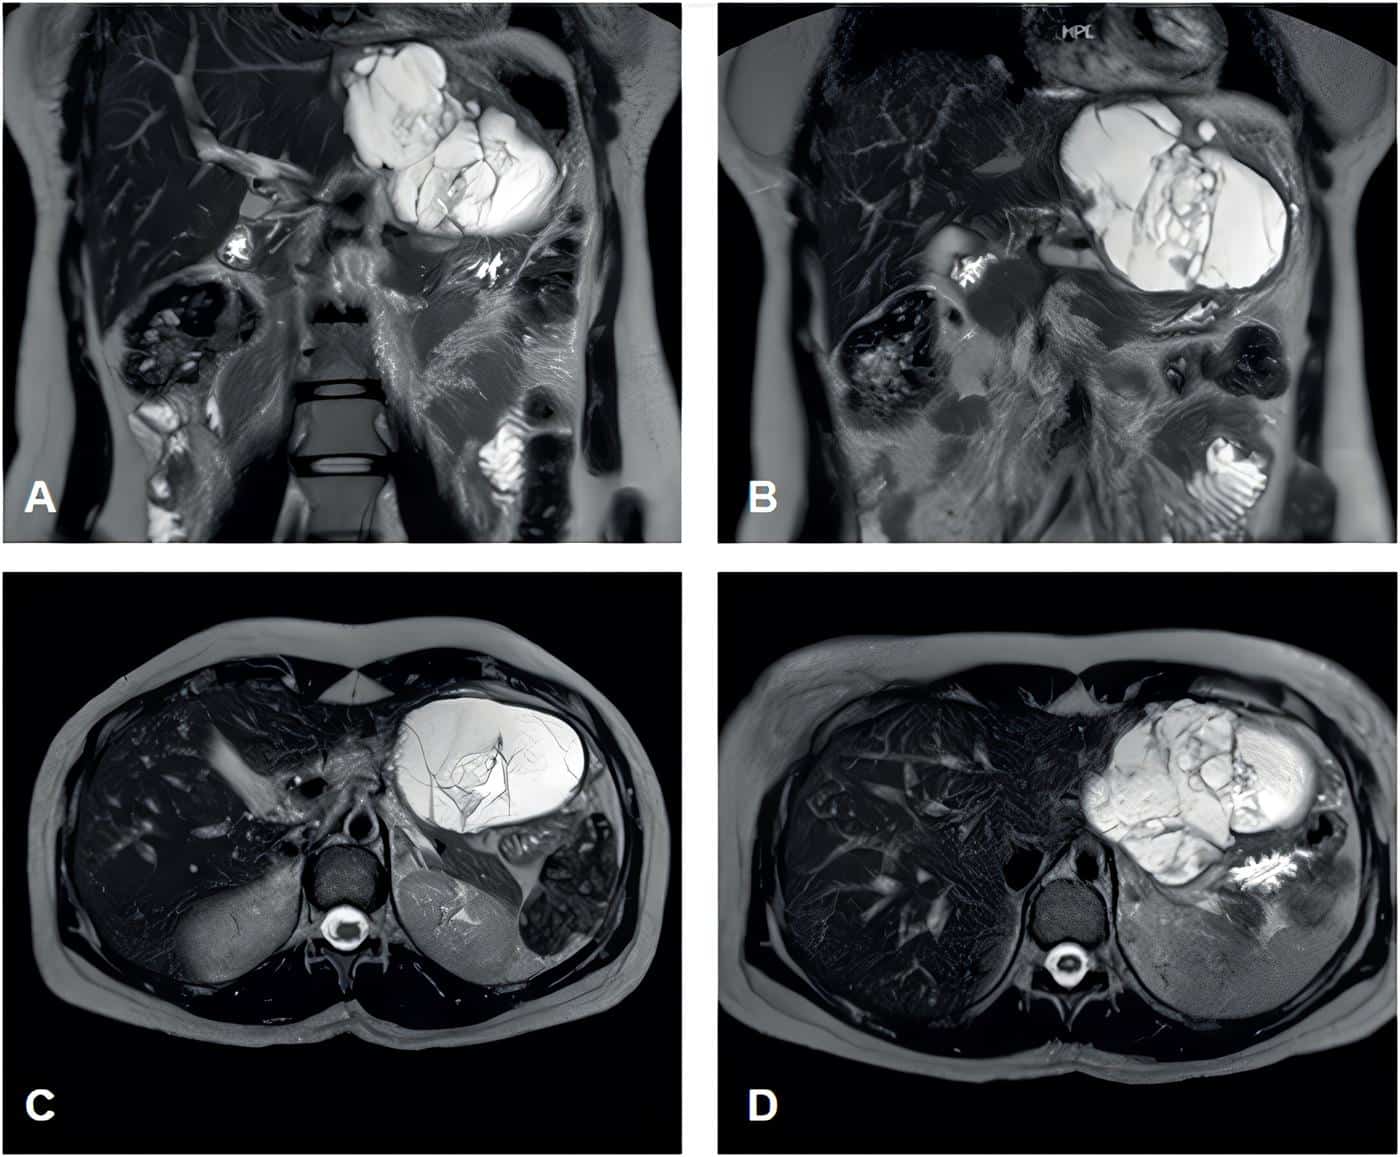

Durante el seguimiento de su enfermedad ginecológica se realizó una resonancia magnética contrastada de abdomen donde se observó una lesión quística en los segmentos II y III del hígado de 10 x 7 x 8 cm, con septos gruesos (Figura 5). Debido a este hallazgo en una paciente asintomática, se decidió programar una hepatectomía por laparoscopia de dichos segmentos.

Figura 5. A-B. Cortes coronales. C-D. Cortes axiales de la colangioresonancia en secuencia T2, donde se puede ver la lesión. Fuente: elaboración por los autores.